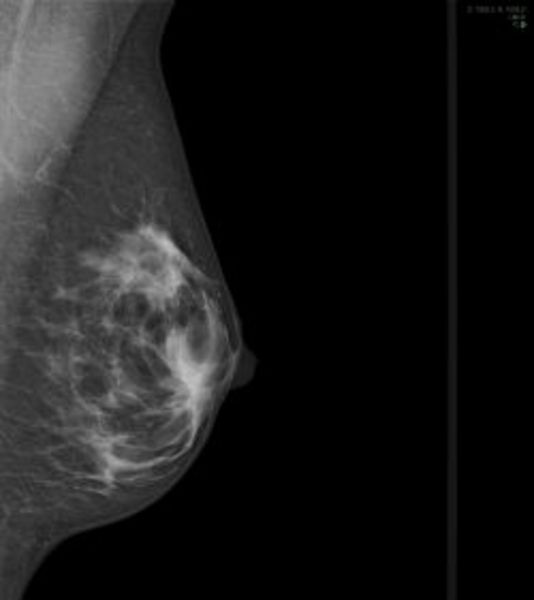

Münster (mfm) - Bösartige Neubildungen der Brustdrüse stehen bei Frauen in Nordrhein-Westfalen an erster Stelle aller Krebserkrankungen. Jede achte Frau muss im Laufe des Lebens mit der Diagnose Brustkrebs rechnen. Um langfristig die Sterblichkeit an Brustkrebs zu senken, wurde 2005 das Mammographie-Screening-Programm eingeführt: Alle Frauen im Alter zwischen 50 und 69 Jahren werden regelmäßig, das heißt, im Abstand von zwei Jahren, zu dieser qualitätsgesicherten Früherkennungsuntersuchung eingeladen.

Einer Arbeitsgruppe aus Vertretern des Epidemiologisches Krebsregisters Nordrhein-Westfalen, des Referenzzentrums Mammographie am Universitätsklinikum Münster und dem Institut für Epidemiologie und Sozialmedizin der Westfälischen Wilhelms-Universität Münster berichtet nun erstmals über die sogenannten Intervallkarzinomraten für das bevölkerungsreichste deutsche Bundesland Nordrhein-Westfalen. Die wissenschaftliche Auswertung der ersten Untersuchungsrunde von Ende 2005 bis Ende 2008 umfasste über 850.000 Screening-Teilnehmerinnen und belegt, dass durch die Screening-Mammographie 7.176 Brustkrebserkrankungen erkannt wurden. In den nachfolgenden zwei Jahren traten unter den beim Screening unauffälligen Frauen weitere 2.036 Fälle von neuem Brustkrebs auf. Durch die Screening-Mammographie als alleiniger Untersuchung konnten damit 78 Prozent aller Brustkrebserkrankungen in dem Zweijahreszeitraum diagnostiziert werden.

Internationale Publikationen lassen vermuten, dass die im Intervall zwischen zwei Screening-Einladungen diagnostizierten Krebsfälle - die sogenannten Intervallkarzinome zumeist neu entstanden sind und zum Screening-Zeitpunkt noch nicht diagnostizierbar waren. Die Ergebnisse entsprechen den Vergleichszahlen aus anderen europäischen Ländern und sind ein Beleg dafür, dass in NRW bereits in der Aufbauphase der systematischen Brustkrebs-Früherkennung die Qualität der Programme in anderen europäischen Ländern erreicht wurde.